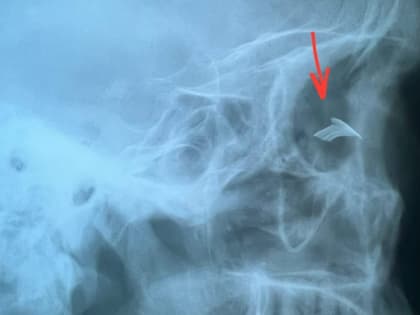

В Чебоксарах офтальмологи спасли глаз пациенту после травмы при строительных работах

В кабинет неотложной помощи Республиканской клинической офтальмологической больницы обращается от 80 до 100 пациентов в сутки, из них около половины с попаданием инородных тел в разные структуры глаза.

В кабинет неотложной помощи Республиканской клинической офтальмологической больницы на днях обратился пациент с травмой глаза.